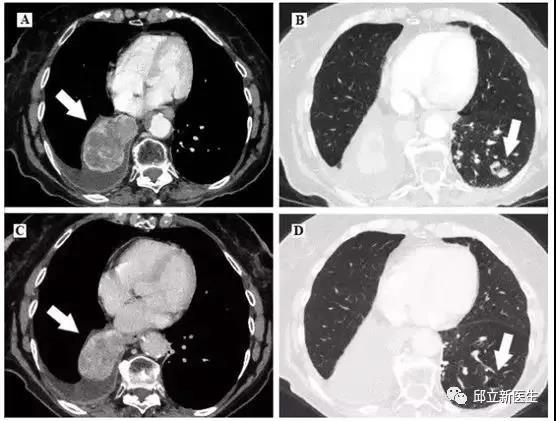

(图像A、B)为给予PD-L1单抗之前;(图像C、D)为给予PD-L1治疗5个月之后;左侧显示肿瘤块,右侧图显示对侧肺部病变。肿瘤体积由75×52毫米缩小到57×40毫米,空洞结节由17×14毫米缩小到13×9毫米。